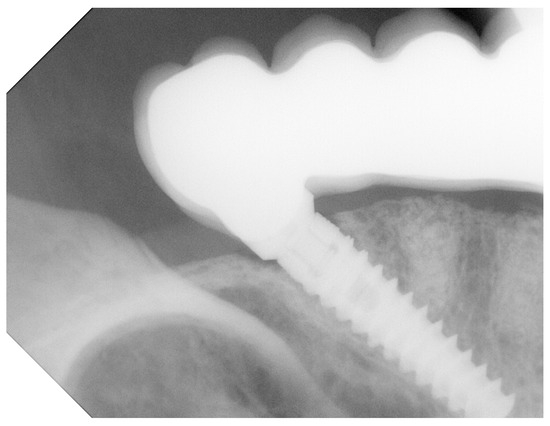

3.3. Bone Loss